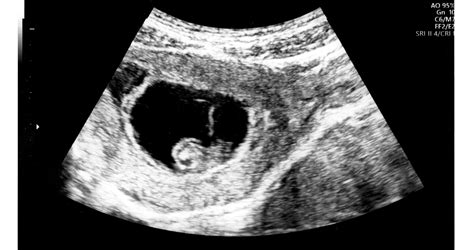

Az orvosok leggyakrabban az ultrahang vizsgálatok során fedezik fel az amnion szalagot. Előfordulhat, hogy az orvos nem mond túl sokat róla, ami aggodalmat kelthet a kismamában, és arra készteti, hogy az interneten keressen további információkat.

Leggyakrabban az amnion szalag jelenléte nem okoz problémát, és a terhesség előrehaladtával már nem is látható az ultrahangon. Azonban, ha a szalag apró részekkel érintkezik, vagy köré csavarodik a magzat valamelyik végtagjának, az problémát jelenthet. Ebben az esetben a baba végtagjai nem tudnak megfelelően fejlődni, és akár végtag-lefűződés is bekövetkezhet. Ez különösen a korai terhességben jelenthet kockázatot, főleg ha elégtelen a magzatvíz mennyisége.

Fontos megjegyezni, hogy amíg a babának van kellő mozgástere a jó mennyiségű magzatvízben, a kötegek nem szoktak problémát okozni. Ezt azonban csak ultrahang vizsgálatot követően lehet eldönteni.